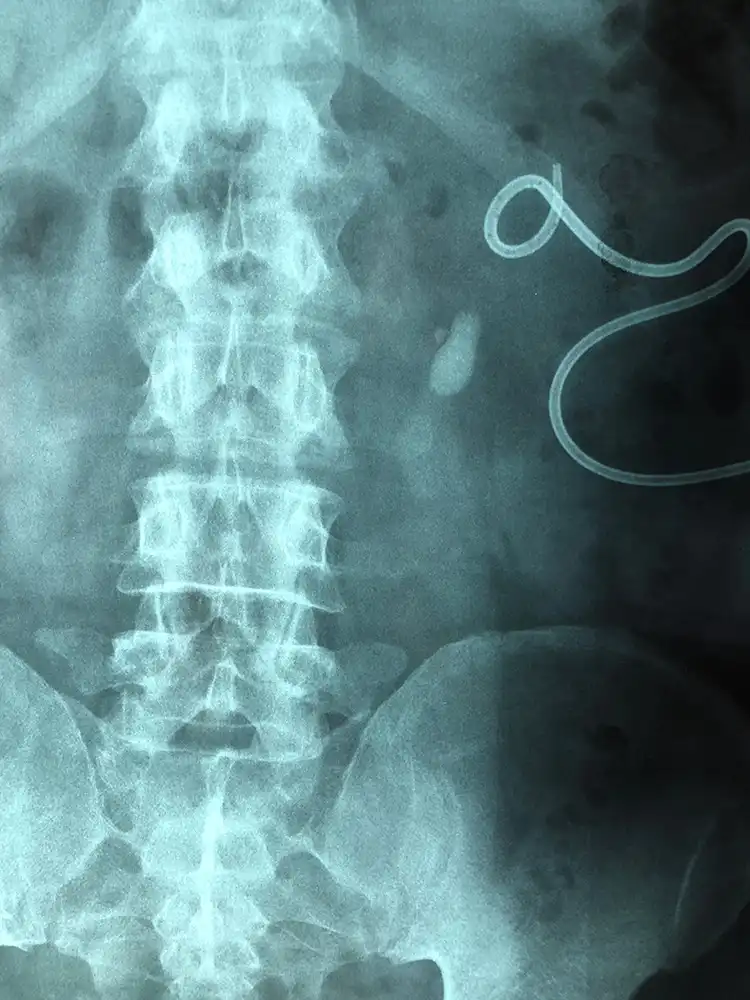

Ασθενής με ευμεγέθη λίθο στο άνω τριτημόριο του αριστερού ουρητήρα, ο οποίος φέρει νεφροστομία λόγω αποφρακτικής ουροπάθειας (Φωτογραφία 1), αντιμετωπίστηκε με laser ουρητηρολιθοθρυψία με ημιάκαμπτο ουρητηροσκόπιο και τοποθέτηση pig-tail με ταυτόχρονη αφαίρεση της νεφροστομίας (Φωτογραφία 2, 1η ημέρα μετεγχειρητικά). Η τρίτη φωτογραφία είναι στις 15 ημέρες πριν την αφαίρεση του pig-tail.